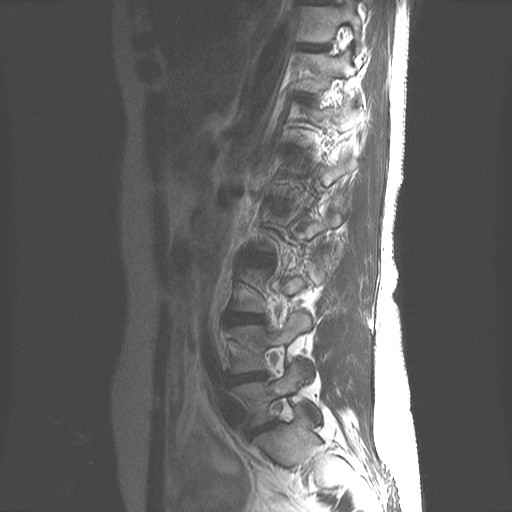

LWZ